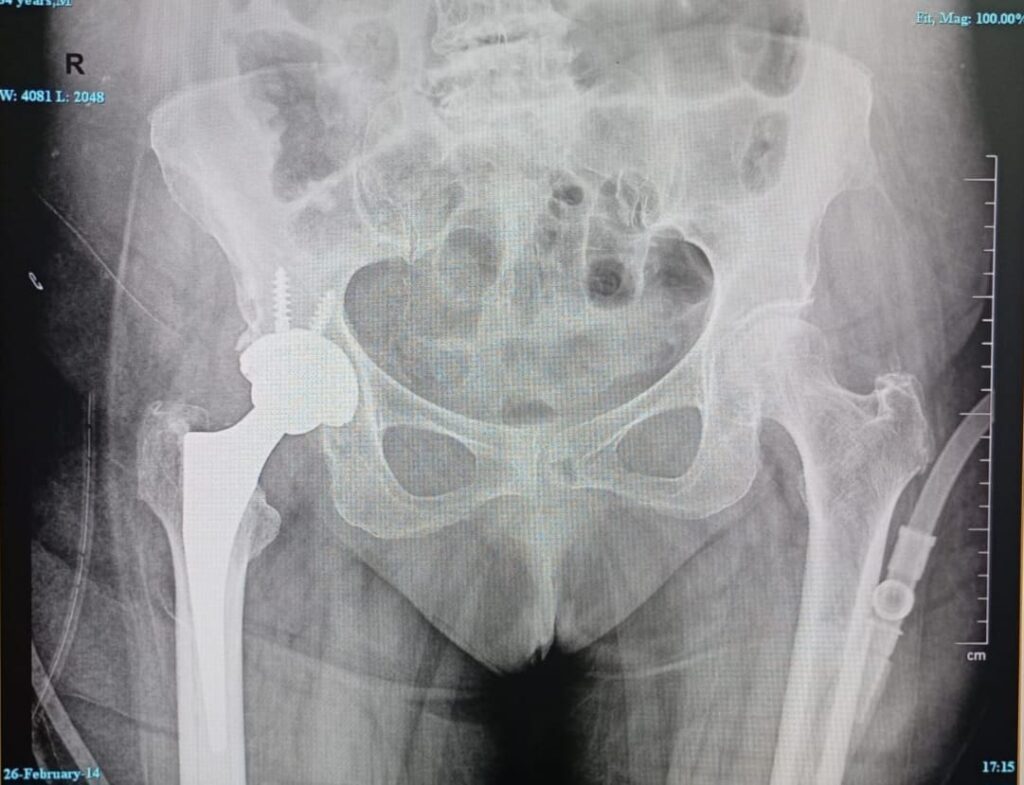

Robotic Joint Replacement Surgery

- Robotic Total Hip Replacement (THR)

- Total Hip Replacement (Conventional)

- Revision Joint Replacement Surgery